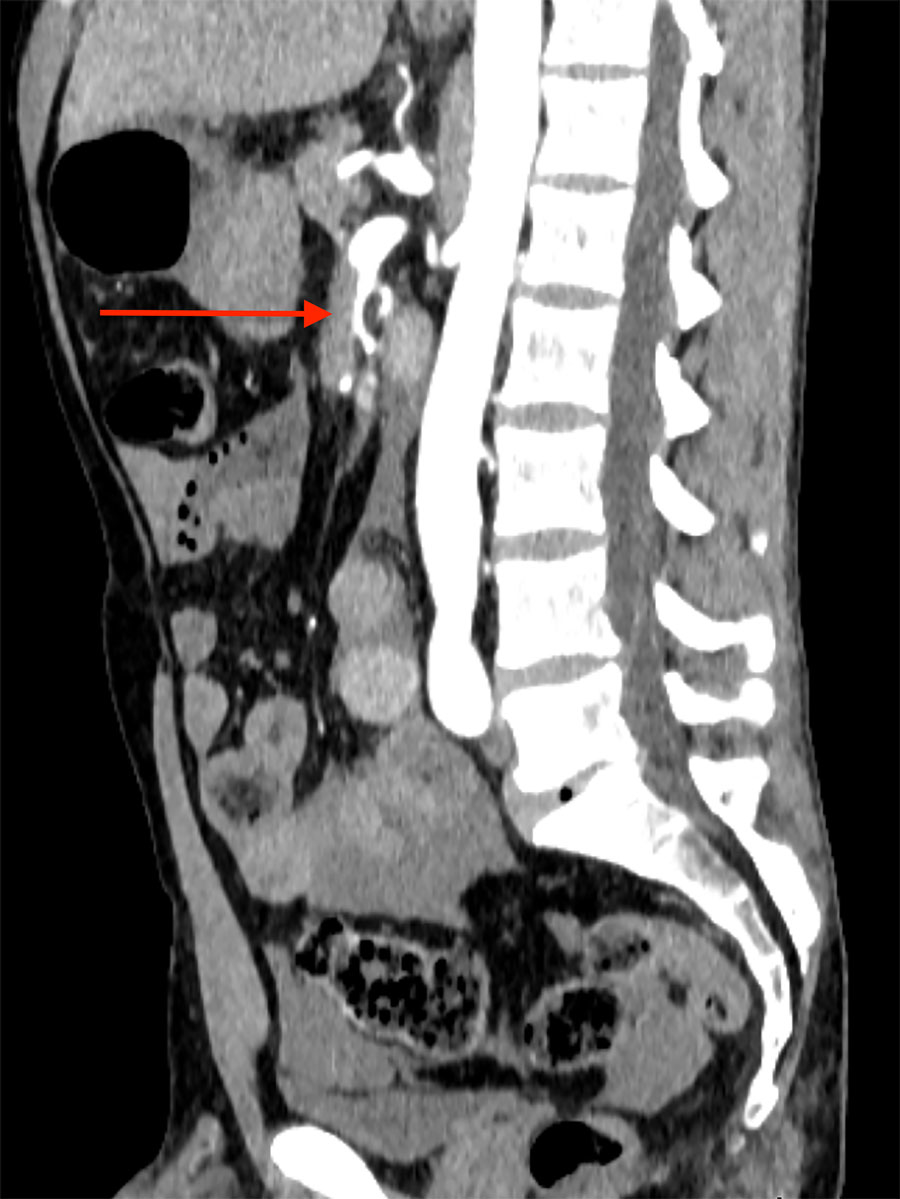

A 42-year-old male was admitted to our emergency department with acute abdominal pain, lipothymia and nausea. The patient was tachycardiac and hypotensive. Physical examination revealed signs of peritonitis. His bloods showed elevated lactates, at 4 mmol/l, while haemoglobin level was normal. The abdominal computed tomography (CT) angiography revealed a massive haemoperitoneum from a ruptured aneurysm of a distal branch of the ascending left colonic artery (fig. 1). Moreover, several aneurysms and strictures of the main intra-abdominal arteries were found, including dissections of both the superior mesenteric and the left common iliac arteries (figs 2 and 3 ).

Figure 2 Emergency abdominal CT scan showing dissection of the superior mesenteric artery (arrow).